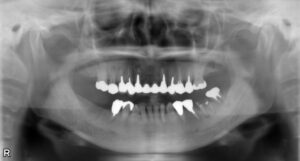

上下5本欠損症例

BEFORE AFTER 62歳女性/上下5本欠損/インプラント埋込手術 【治療内容】 欠損歯が多いため、お食事が取りに…